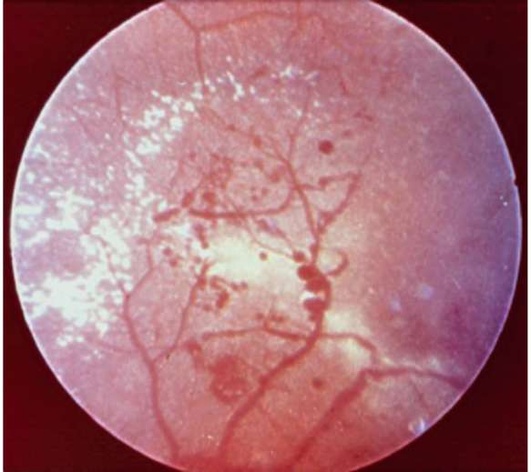

Рис. 33.4. Изменения на глазном дне при диабетической ретинопатии